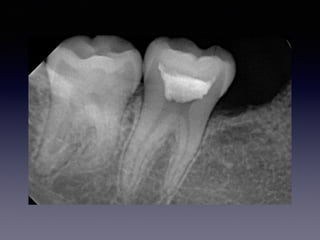

#30 Partial pulpotomy follow-upcase

(23 female)

2013 01 26 201210 13 23m later